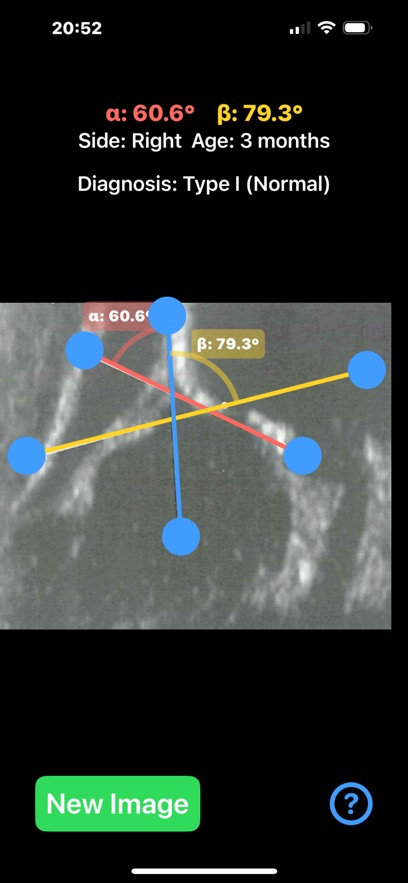

Ultrasonography, rather than X-ray, is the preferred method for diagnosing DDH in infants, especially under the age of 6 months. Ultrasound provides a non-invasive and radiation-free way to visualize the soft tissues, cartilage, and bones in real time. The Graf method is the most widely used technique, where two critical angles—alpha (α) and beta (β)—are measured to assess the development of the acetabulum and classify the hip's condition.This application is designed to aid healthcare professionals—especially radiologists, orthopaedic surgeons—in evaluating DDH by calculating the alpha (α) and beta (β) angles quickl from saved ultrasound images of the patient hip.

Provide instant visual feedback by color-coding the angles:Alpha angle (α): red, Beta angle (β): yellow. Automatically also classify the hip joint based on the Graf method Type I,Type IIa/b,Type IIc,Type III, helping clinicians to have a quick glimpse and visualise the relationship between the angles ,real time.Healthcare professionals, particularly in busy departments, can save significant time by quickly loading ultrasound images and automating angle calculations, identify abnormal hips on the go . App can also be used as a training tool for medical students, residents, and junior clinicians, teaching them how to recognise key landmarks, make accurate measurements, and classify DDH using ultrasound images. By rapid visually displaying the measurements on the screen and generating easy-to-understand images, app helps clinicians explain the condition and its severity to parents.

App offers α and β angle measurement by dragging points on the ultrasound image to key anatomical landmarks, forming lines that define the acetabular roof and cartilaginous roof. The app automatically calculates the angles and classifies the hip condition based on these measurements in real-time.

Important feedback that help allow the user to adjust draggable points and see immediate changes in the angle values helping to fine-tune the position of the lines and target the preferred anatomical landmarks of the ultrasound image more efficiently. User-friendly interface, and reliable classification system based on Graf’s classification that streamline the diagnostic process, and improved overall workflow in clinical practice.